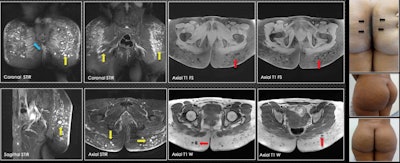

A 35-year-old patient was injected with biopolymers in the gluteal region five years ago. Three years later, changes in the coloration of the skin are visible between the gluteal folds (blue arrows). On MRI, there are multiple vacuoles of hyperintense behavior in the short-tau inversion recovery sequences (yellow arrows) and vacuoles of hypointense behavior in the sequences with T1-weighted information (red arrows), which are compatible with biopolymers located mainly in subcutaneous tissue. In the gluteus maximus muscle, biopolymers are seen in the fusion form (blue arrow). No vacuoles were identified at this level.A few weeks after placing the biopolymers, liquid forms can be seen that simulate seromas without vesicles. After six to 12 months, seromas and vesicles coexist. After more than 18 months, only vesicles containing the biopolymer material are found. In many patients, there is migration from deep to superficial planes, which, due to their shape and distribution, suggests that lymphatic drainage has occurred.